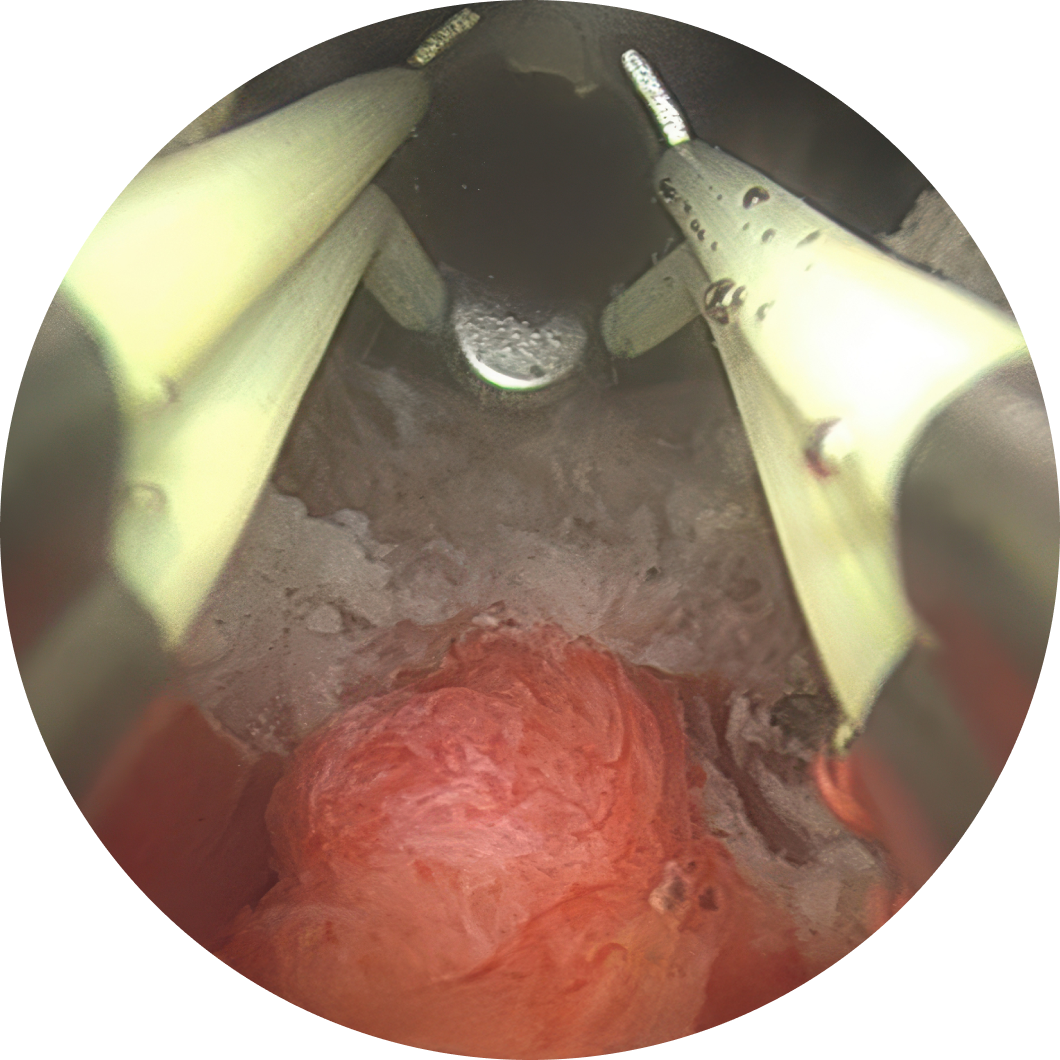

절제 부위를 정확히 지정합니다.

먼저 국내 조기 도입 이후 축적된 500례 이상의 수술 경험을 바탕으로 환자별 전립선 크기와 형태에 맞는 절제 범위를 계획하고 있으며, 실시간 초음파 영상과 AI 기반 수술 설계를 함께 활용해 밀리미터 단위의 정교한 절제를 시행하고 있습니다.

또한 사정 기능과 관련된 정구 주변 미세 구조를 보존하기 위한 Hood Sparing 기법을 적용하여 역행성 사정 발생률을 기존보다 ½로 감소시켰습니다. 이러한 배뇨 개선과 기능 보존을 동시에 고려한 접근은 역행성 사정 발생 가능성을 낮추는 데 도움이 될 수 있습니다.

예를 들어 골드만비뇨의학과에서는 아쿠아블레이션을 국내 조기 도입 이후 축적된 500례 이상의 수술 경험을 바탕으로 환자별 전립선 구조에 맞는 절제 범위를 설계하고 있습니다. 또한 AI 기반 수술 계획과 실시간 초음파 영상을 함께 활용해 밀리미터 단위의 정밀 절제를 진행하며, 사정 기능 보존과 관련된 정구 주변 미세 구조를 고려한 Hood Sparing 기법을 적용하고 있습니다.